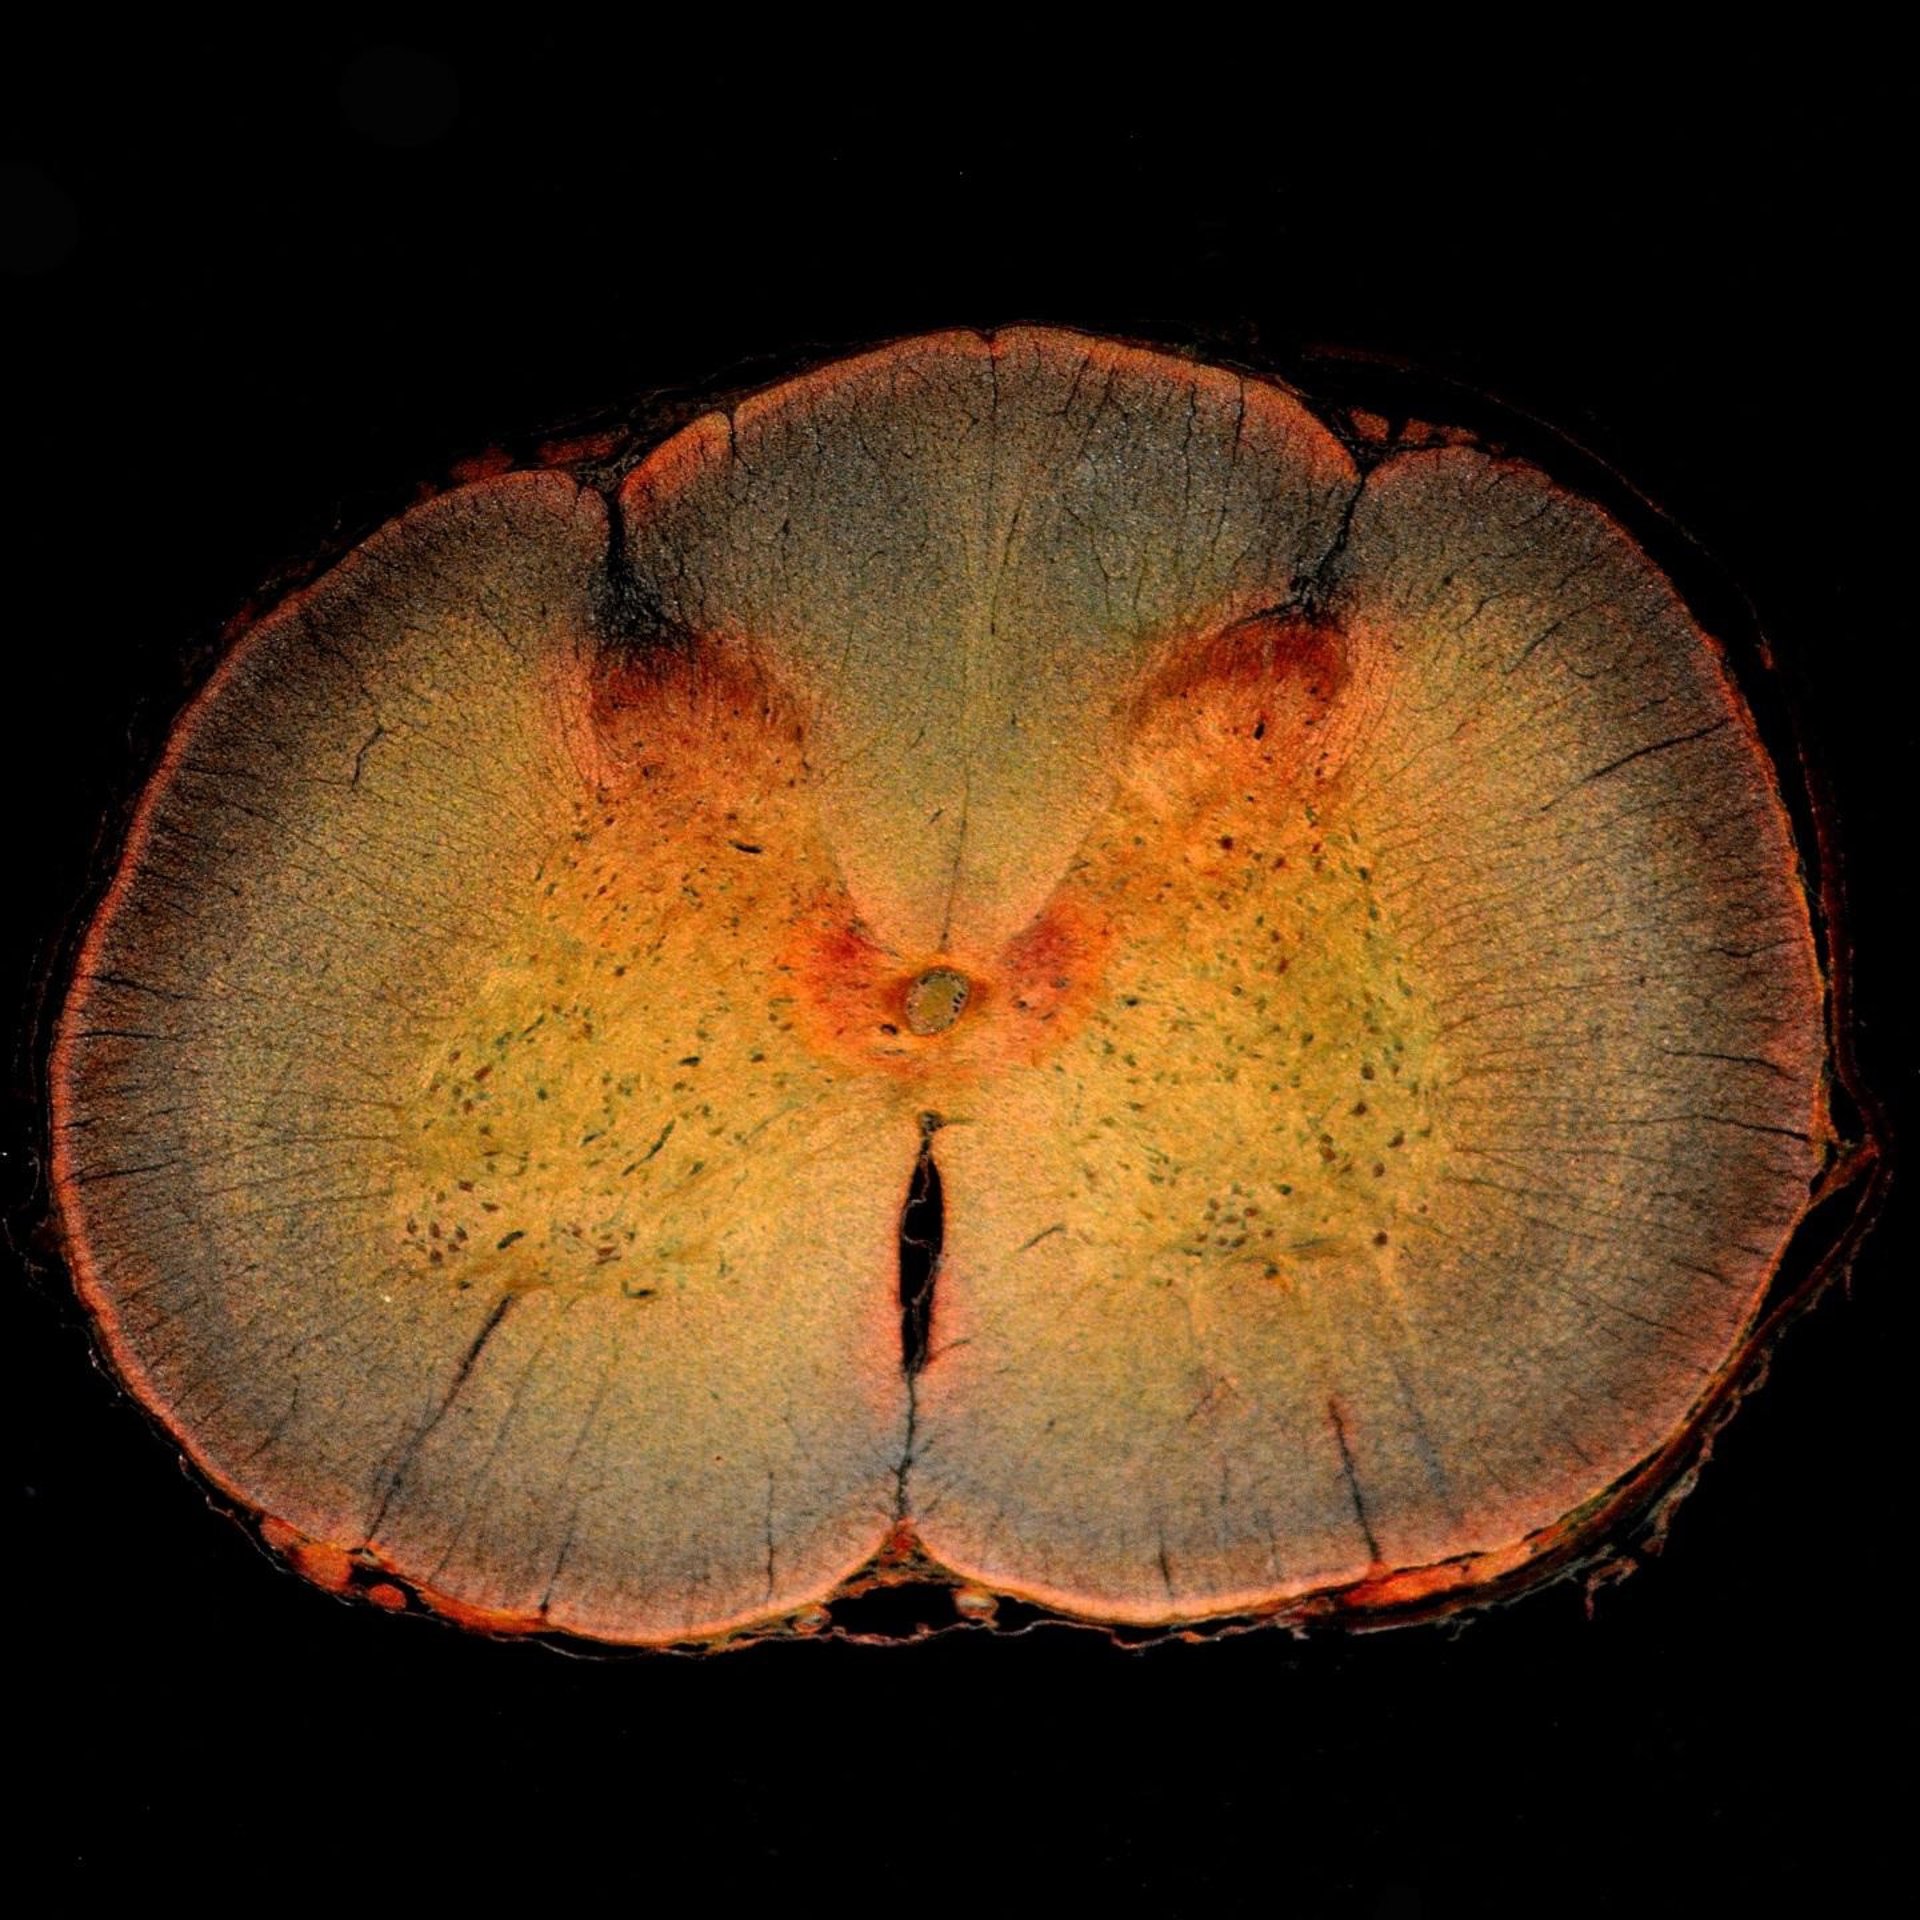

Sección transversal de la médula espinal, incluido el cuerno dorsal de la médula espinal, donde se procesa el dolor.

Sección transversal de la médula espinal, incluido el cuerno dorsal de la médula espinal, donde se procesa el dolor. - DW_ROSS / FLICKR - Archivo